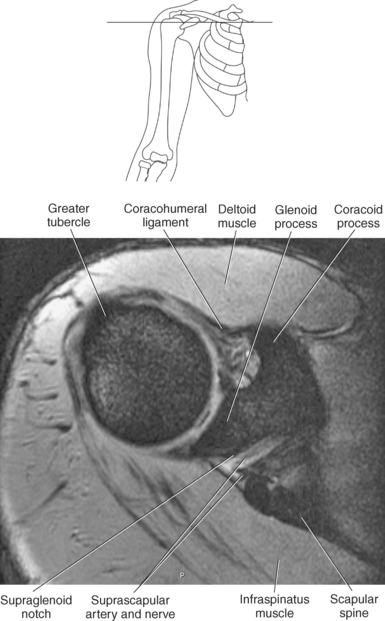

The scapula is a triangular-shaped flat bone that forms the posterior portion of the shoulder girdle. It has a medial margin, a lateral margin, and a superior margin. The margins are separated by the superior, inferior, and lateral angles (Figures 9.2 and 9.3). The anterior surface of the scapula, subscapular fossa, is flat and slightly concave. The posterior surface of the scapula is divided by the scapular spine into a smaller supraspinous fossa, and a larger infraspinous fossa (Figure 9.7). Four projections of the scapula provide attachment sites for the muscles and ligaments contributing to the shoulder girdle. These include the scapular spine, acromion, coracoid process, and glenoid process (Figures 9.7 through 9.10). The scapular spine arises from the upper third of the posterior surface of the scapula and extends obliquely and laterally to give rise to a flattened process termed the acromion. Located on the anterolateral surface of the scapula is a beaklike process termed the coracoid process, which arises just medial to the glenoid process and functions to protect the shoulder joint, which lies beneath it. The coracoid process is an attachment site for the pectoralis minor, short head of the biceps brachii, and the coracobrachialis muscles. The scapular notch is located just medial to the coracoid process, on the superior margin of the scapula and allows for the passage of the suprascapular nerve (Figure 9.2). The glenoid process, the largest of the projections, forms the lateral angle of the scapula and ends in a depression called the glenoid fossa (glenoid cavity) (Figures 9.7 through 9.9). There are two tubercles associated with the glenoid fossa, an upper supraglenoid tubercle and a lower infraglenoid tubercle, which serve as attachment sites for the biceps brachii and triceps brachii (Figure 9.8). The shallow articular surface of the glenoid fossa joins with the relatively large articular surface of the humeral head to create the freely moving glenohumeral joint (Figures 9.2, 9.3, 9.11, and 9.12).

The edge of the glenoid fossa is surrounded by a fibrocartilaginous ring termed the glenoid labrum (glenoid lip) (Figure 9.17). The glenoid labrum is a fold of the articular capsule, which functions to deepen the articular surface of the glenoid fossa. Superiorly, the labrum blends with the long head of the biceps brachii muscle. In cross section it appears triangular (Figure 9.18). The three glenohumeral ligaments (superior middle, and inferior) are thickenings of the fibrous capsule that surrounds the shoulder joint; they contributes to the formation of the glenoid labrum (Figures 9.17 and 9.19). They extend from the supraglenoid tubercle of the scapula to the lesser tubercle of the humerus. Also aiding in strengthening the fibrous capsule is the coracohumeral ligament that passes from the lateral side of the coracoid process of the scapula to the anatomic neck of the humerus (Figure 9.19). The coracoacromial ligament is another important ligament located on the anterior portion of the shoulder. As this ligament joins the coracoid process and acromion, it forms a strong bridge, termed the coracoacromial arch, which protects the humeral head and rotator cuff tendons from direct trauma and prevents displacement of the humeral head superiorly (Figures 9.17 and 9.19). The coracoclavicular ligaments help to maintain the position of the clavicle, in relation to the acromion, by spanning the distance between the clavicle and coracoid process of the scapula (Figure 9.19). The acromioclavicular ligament, at the acromioclavicular joint, provides support for the superior surface of the shoulder (Figures 9.17 and 9.19). The transverse humeral ligament is a broad band of connective tissue passing from the greater tubercle to the lesser tubercle of the humerus, forming a bridge over the intertubercular groove for protection of the long head of the biceps tendon (Figure 9.19). The ligaments of the shoulder are demonstrated in Figures 9.20 through 9.30.

Muscles of the scapula are described in Table 9.2 and demonstrated in Figures 9.34 through 9.52. The large deltoid muscle originates on the clavicle, acromion, and scapular spine to blanket the shoulder joint as it extends to insert on the deltoid tuberosity of the humerus. This powerful muscle forms the rounded contour of the shoulder and functions primarily to abduct the arm (Figure 9.48). The teres major muscle is a flat rectangular muscle that adducts and medially rotates the arm. It extends from the inferior angle of the scapula to the medial aspect or lip of the intertubercular groove of the humerus (Figure 9.49, A). The four remaining muscles, supraspinatus, infraspinatus, teres minor, and subscapularis, closely surround the scapula and compose the rotator cuff (Figures 9.49 through 9.52). The rotator cuff provides dynamic stability to the shoulder joint and allows for adduction, abduction, and rotation of the humerus. The supraspinatus, infraspinatus, and teres minor muscles are located on the posterior aspect of the scapula. The tendons of these muscles insert on the greater tubercle of the humerus. The supraspinatus muscle lies in the supraspinous fossa of the scapula and helps to abduct the arm. The tendon of the supraspinatus muscle is the most frequently injured tendon of the rotator cuff because of possible impingement as it extends under the acromioclavicular joint and continues over the humeral head (Figure 9.49, B). The infraspinatus muscle is a triangular muscle that lies below the scapular spine in the infraspinous fossa. It acts to laterally rotate the arm (Figure 9.49, A). Lying along the inferior border of the infraspinatus muscle is the elongated teres minor muscle, which also acts to laterally rotate the arm (Figure 9.49, B). The subscapularis muscle is the only muscle of the rotator cuff located on the anterior surface of the scapula; its tendon inserts on the lesser tubercle of the humerus (Figures 9.50 through 9.52). The subscapularis muscle acts to medially rotate the humerus. See sequential images through the shoulder (Figures 9.34 through 9.47).